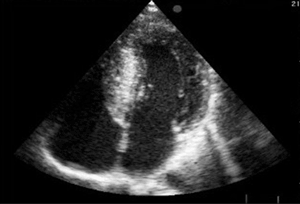

La distribución de la hipertrofia en la pared ventricular es variable, aunque en su forma más típica predomina en el sector anterior del septum interventricular basal (figura 1), dando fundamento a la denominación con que Teare hizo conocer la entidad en su publicación original: hipertrofia septal asimétrica (3). Sin embargo, este no es un requisito excluyente, y cualquier patrón de distribución es posible, como lo han demostrado las revisiones ecocardiográficas (5) y especialmente los más recientes estudios con resonancia nuclear magnética (6,7).

Figura 1. Ecocardiograma bidimensional. Enfoque apical de cuatro cámaras. Severa hipertrofia asimétrica a predominio del septum basal y medio en un paciente no hipertenso.